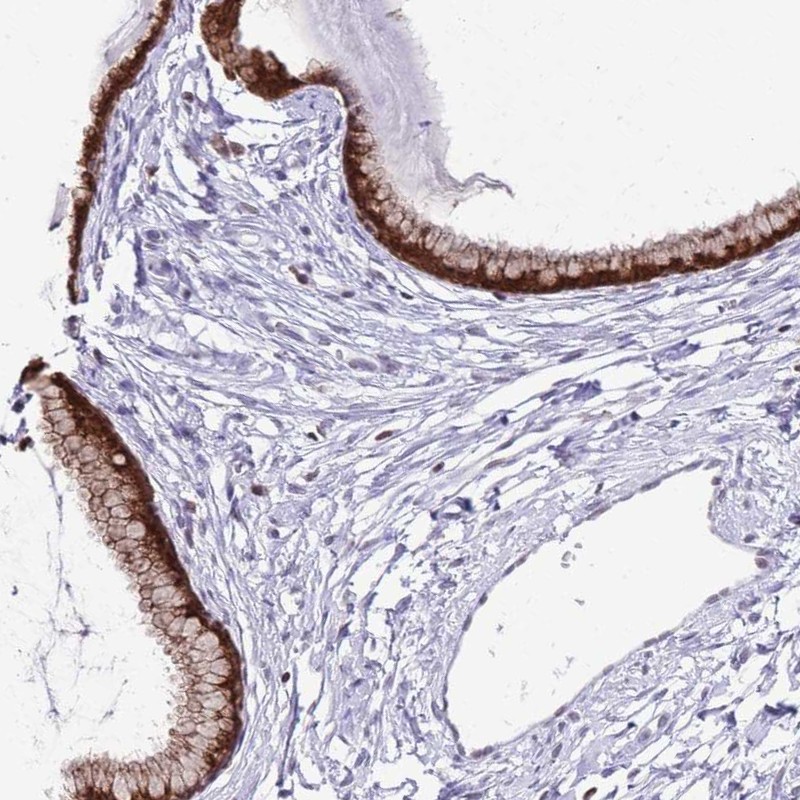

Immunohistochemistry analysis in human cervix, uterine and prostate tissues using Anti-PRR15 antibody. Corresponding PRR15 RNA-seq data are presented for the same tissues.